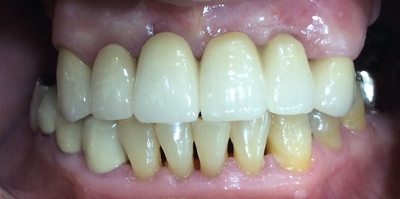

브릿지 완성된 모습입니다.

PFM 브릿지로 PFM보다 다른 재료를 선택하셨으면 조금 더 자연스러울 수 있었을 것으로 예상합니다.

브릿지를 한 모습입니다.

브릿지 하시고 웃을 때 모습입니다.

이 상태로도 웃을 때나 말할 때 티가 안난다며 굉장히 만족하셨습니다.